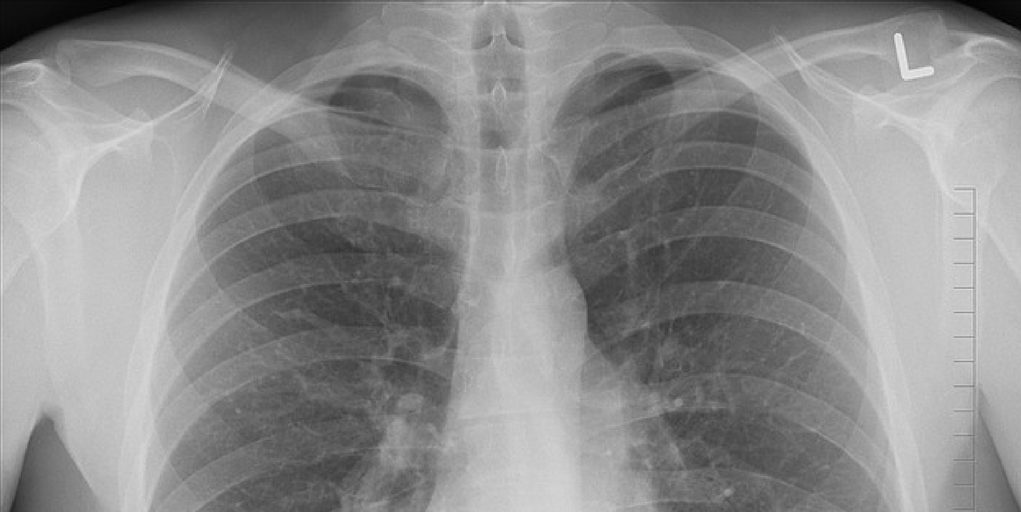

The aim of the study is identifying who is more at risk for developing chronic lung diseases such as chronic obstructive pulmonary disease (COPD), emphysema and pulmonary fibrosis. “The long-term impact of e-cigarettes and vaping is not known, and it is possible these habits are as harmful as smoking,” said Mark Dransfield, M.D., the William C. Bailey Endowed Chair in Pulmonary Disease. “It is critically important we understand their health effects as millions of young people are now using these products.”